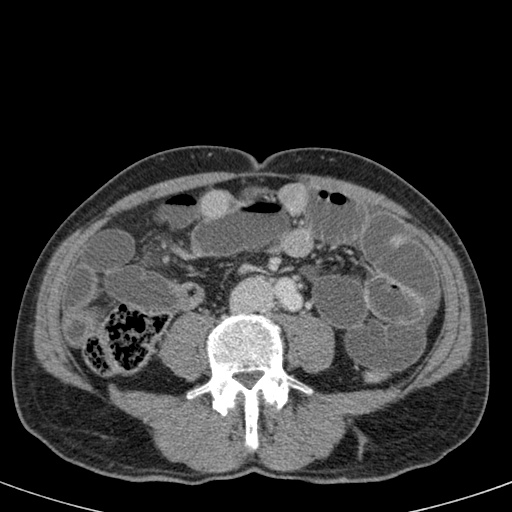

Đây là một bệnh nhân bị tắc ruột non.

Cuộn qua các hình ảnh.

Bạn có thể tìm thấy quai kín và nguyên nhân gây ra nó không?

Khi tiếp nhận bệnh nhân tại phòng cấp cứu với biểu hiện nghi ngờ tắc ruột non (SBO), điều quan trọng nhất chúng ta cần làm, ngoài việc chẩn đoán xác định, là xác định sự hiện diện hay vắng mặt của tình trạng thắt nghẹt.

CT là phương pháp chẩn đoán hình ảnh được lựa chọn trong đánh giá bệnh nhân nghi ngờ tắc ruột non.

Hình ảnh CT của tắc ruột non dạng quai kín phụ thuộc vào hai yếu tố:

- chiều dài đoạn ruột tạo thành quai kín

- hướng của quai ruột so với mặt phẳng tạo ảnh

Nếu quai kín ngắn và nằm trong mặt phẳng tạo ảnh, chúng ta sẽ thấy quai ruột hình chữ U hoặc chữ C.